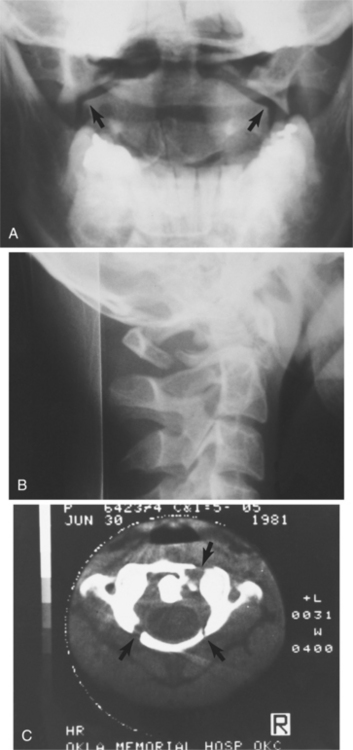

Fig. 34-14 shows a Jefferson fracture seen on x-ray and magnetic resonance imaging (MRI) scan. Fig. 34-15 compares fractures at time of injury and after stabilization. Myelography is indicated for optimal visualization of compression of the spinal cord after trauma. Myelography alone is rarely indicated, and it is used in conjunction with CT. In many cases, MRI has replaced myelography.

Figure 34-14 Fracture of C1 (Jefferson fracture). A, Anteroposterior view showing lateral displacement of the lateral mass and articulating facets of C1 on C2. B, Oblique view illustrating disruption of the posterior aspect of the ring of C1. C, Computed tomographic scan revealing the true extent of the injury. (From Green NE, Swiotkowski MF, eds: Skeletal trauma in children, ed 3, Philadelphia, 2003, Saunders. Courtesy of Dr. Teresa Stacy.)